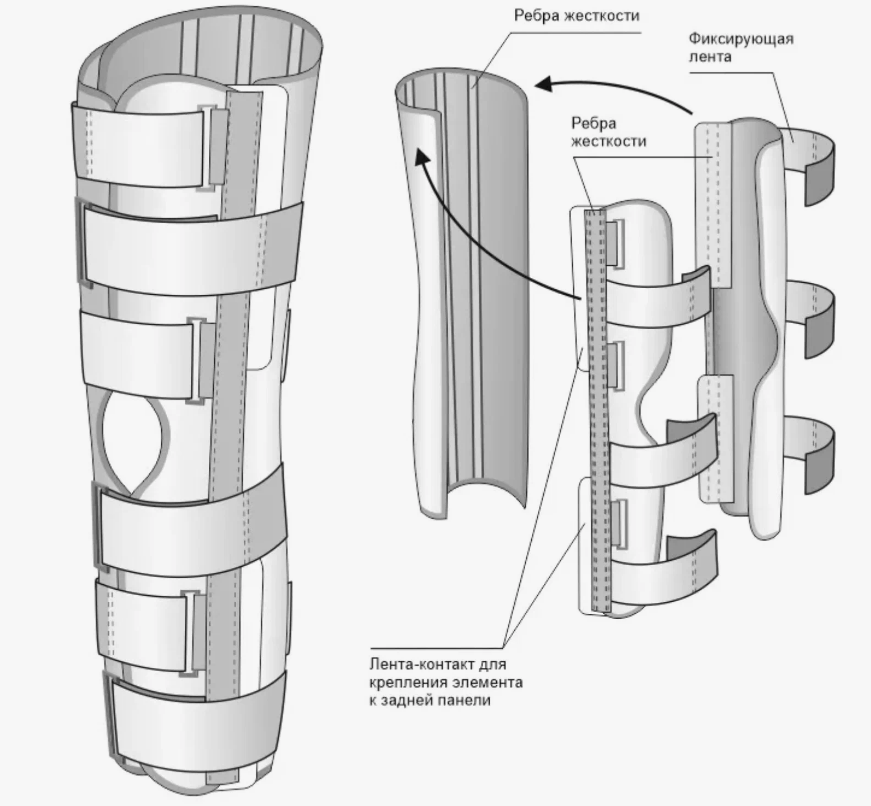

Ортез Orlett на коленный сустав (тутор на коленный сустав) предназначен для иммобилизации (полной фиксации) коленного сустава. Фиксация достигается при помощи 5-ти съемных металлических шин и манжет с ремнями-затяжками, снабженными застежками-липучками «Велкро» (от 4 до 6 в зависимости от размера).

- Предусмотрена возможность индивидуального моделирования металлических шин.

- Длина тутора и количество фиксирующих ремней увеличиваются в зависимости от размера ортеза.

| Конструкция | разъемный, с ребрами жесткости |